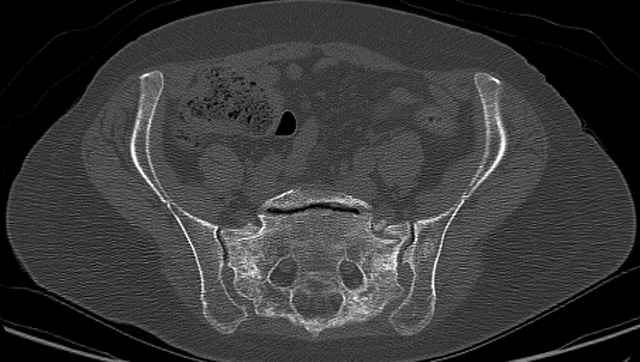

Here are a recent patient’s example slides...

54 yo Female Fell c/o Pain

Initial Films

?Instability on Exam - Limited by Pain

NonOp Initial Mgmt

3 Months After Fall

Continued Pain & Immobility

(+) Instability to Compressive Manual Exam

Pelvic CT Scan - 3 Months After Fall

Sacral Injuries

Ramus Fractures